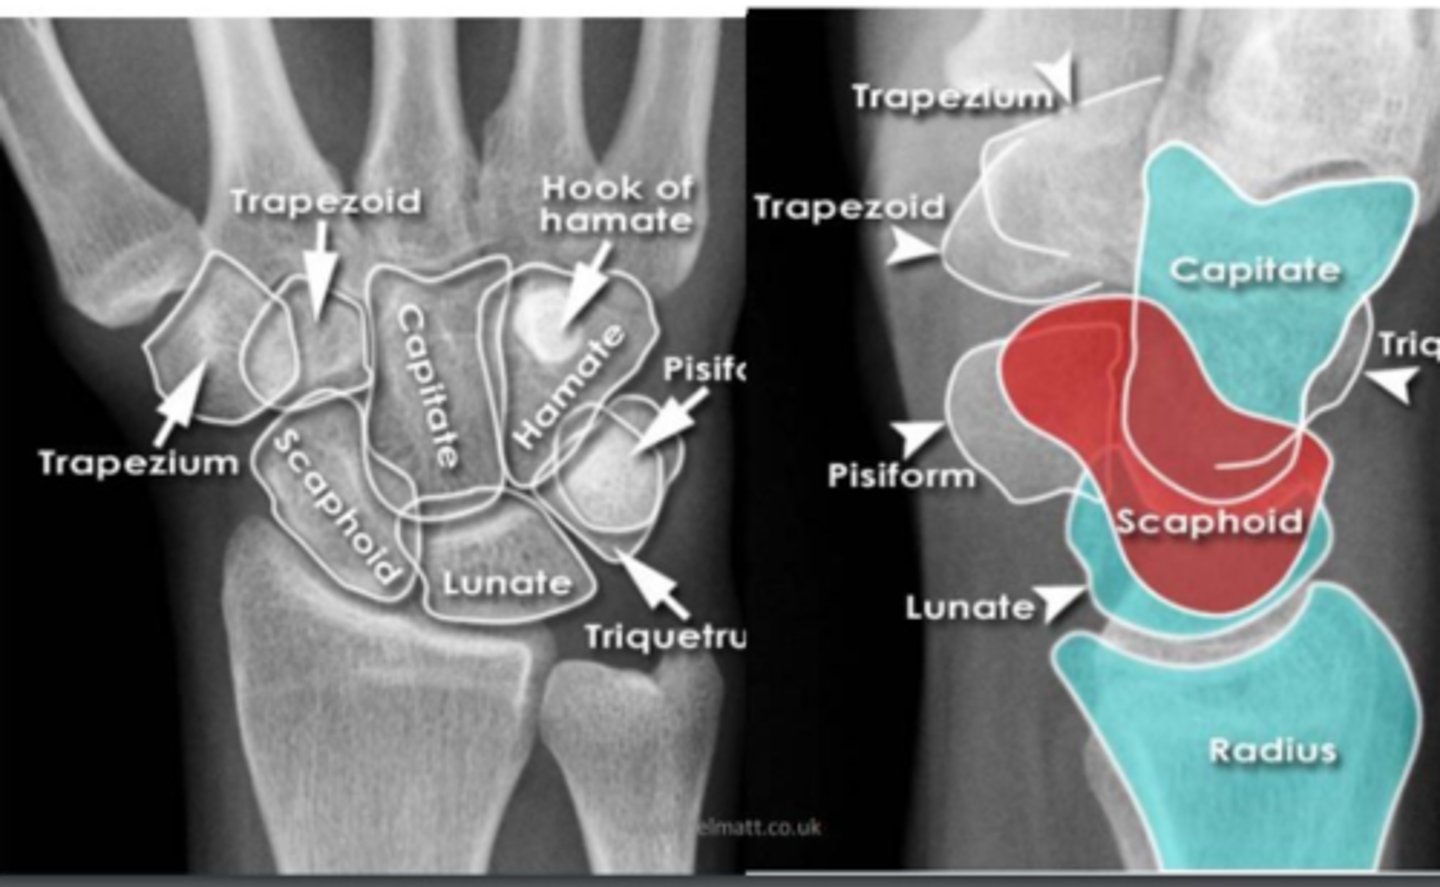

wrist

knowt flashcard image